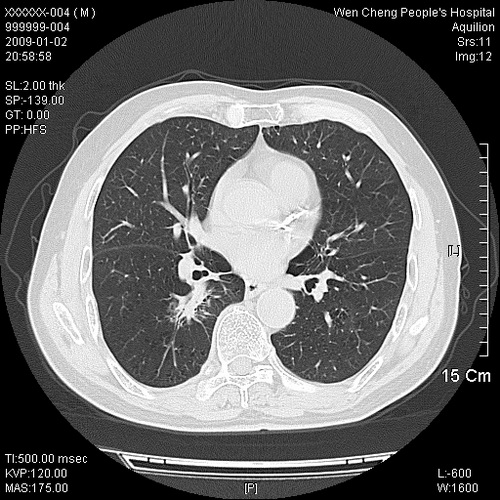

男性,73岁,有慢支病史,肿瘤系列标志物检验正常,血沉及血常规正常

右肺下叶背段小片状 磨玻璃样模糊影,内见血管及含气支气管像,支气管管壁增厚。考虑:慢性炎症!

右肺下叶背段小片状 实性与磨玻璃样影,内见血管及含气支气管像,支气管管壁增厚,边缘见长毛刺影。考虑:慢性炎症或肿瘤!建议抗炎治疗复查,密切观察随访!

右肺下叶片团状影内见扩张的含气支气管和支气管管壁增厚,其周有磨玻璃样模糊影和长毛刺。考虑慢性炎症可能性大。

2、右肺下叶片团状影内见扩张的含气支气管和支气管管壁增厚,其周有磨玻璃样模糊影和长毛刺。考虑周围型肺ca可能,结核不排。

高度提示细支气管肺泡癌,建议抗炎治疗半月观察病灶变化,如无明显改变,建议立即手术治疗.